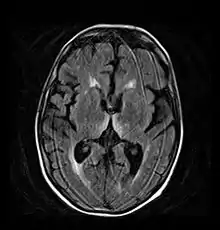

Brain atrophy associated with WKS occurs in the following regions of the brain: the mammillary bodies, the thalamus, the periaqueductal grey, the walls of the 3rd ventricle, the floor of the 4th ventricle, the cerebellum, and the frontal lobe. In addition to the damage seen in these areas there have been reports of damage to cortex, although it was noted that this may be due to the direct toxic effects of alcohol as opposed to thiamine deficiency that has been attributed as the underlying cause of Wernicke-Korsakoff Syndrome.[28]

The amnesia that is associated with this syndrome is a result of the atrophy in the structures of the diencephalon (the thalamus, hypothalamus and mammillary bodies), and is similar to amnesia that is presented as a result of other cases of damage to the medial temporal lobe.[29] It has been argued that the memory impairments can occur as a result of damage along any part of the mammillo-thalamic tract, which explains how WKS can develop in patients with damage exclusively to either the thalamus or the mammillary bodies.[28]

Frequently, secondary to thiamine deficiency and subsequent cytotoxic edema in Wernicke encephalopathy, patients will have marked degeneration of the mammillary bodies. Thiamine (vitamin B1) is an essential coenzyme in carbohydrate metabolism and is also a regulator of osmotic gradient. Its deficiency may cause swelling of the intracellular space and local disruption of the blood-brain barrier. Brain tissue is very sensitive to changes in electrolytes and pressure and edema can be cytotoxic. In Wernicke this occurs specifically in the mammillary bodies, medial thalami, tectal plate, and periaqueductal areas. Sufferers may also exhibit a dislike for sunlight and so may wish to stay indoors with the lights off. The mechanism of this degeneration is unknown, but it supports the current neurological theory that the mammillary bodies play a role in various "memory circuits" within the brain. An example of a memory circuit is the Papez circuit.